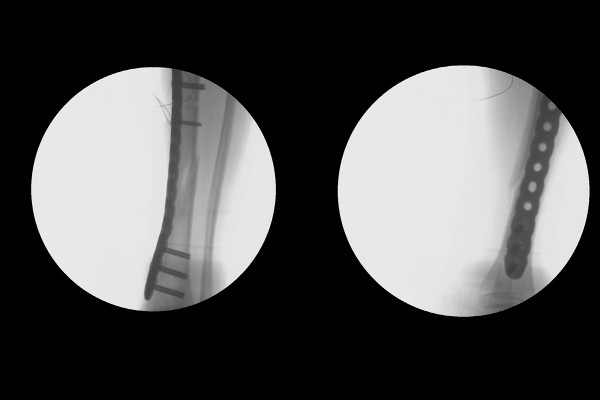

환자분과 보호자분께 현재 뼈 상태와 수술적 치료의 필요성을 설명드렸고, 소아 정강이뼈 골절정복술 및 내고정술(ORIF c MIPO plate for Fx. distal dibia shaft lowerleg Lt.)을 시행하였습니다.

실시간 X-RAY인 C-ARM을 이용해 확인하면서 어긋나있던 골절선을 맞추어 올바른 정렬을 이루게 한 뒤, 금속판(Plate)으로 강하게 고정해줍니다.